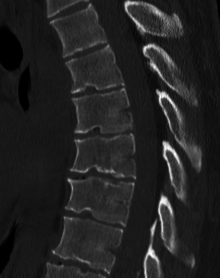

| A 20-year-old male with Scheuermann's disease, showing various measurement of kyphotic/lordotic degrees and their supplementary angles. Notice the signature 'wedging' shape of the four vertebrae in the lower thoracic area. The other vertebral bodies are otherwise normal. The measured kyphosis for this patient is ~70°. | |

Scheuermann's disease is a self-limiting skeletal disorder of childhood. Scheuermann's disease describes a condition where the vertebrae grow unevenly with respect to the sagittal plane; that is, the posterior angle is often greater than the anterior. This uneven growth results in the signature "wedging" shape of the vertebrae, causing kyphosis. It is named after Holger Werfel Scheuermann.[1][2][3]